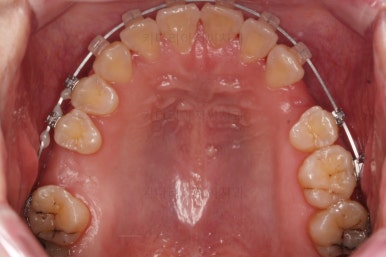

초진 시 입안의 모습입니다.

당장 눈에 띄는 부분은 아래 앞니 사이에 틈새가 있어 치석도 많이 쌓여있는 상황이고요.

윗니-아랫니를 각각 보면 치아가 썩고 부러져 뿌리만 남은 치아가 많이 보입니다.

남은 치아들도 곳곳에 충치가 보이고요.

또 전반적으로 앞니가 앞으로 밀려나와 뻐드러져 있는 모습도 관찰되네요.